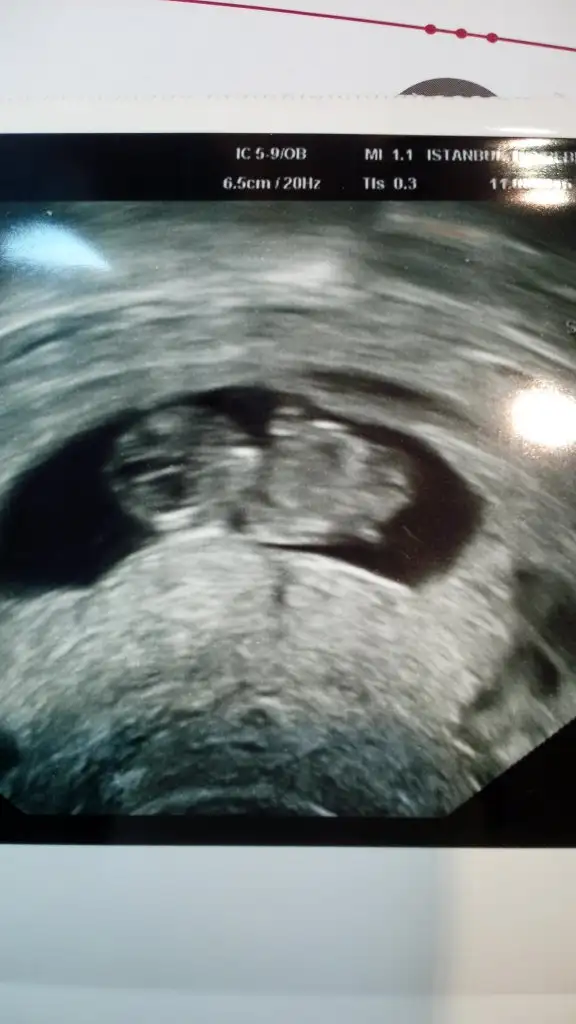

Bence erkek kese fasulye seklinde ve kiz bukadar cabuk sekillenirmi bilemedim ...

:) eşimde diyor heryeri belli erkek doktor oldu başımaBence erkek kese fasulye seklinde ve kiz bukadar cabuk sekillenirmi bilemedim ...

Erkek..Bide yorum istiyom foto attım

Bencede erkekBide yorum istiyom foto attım

Bu foto